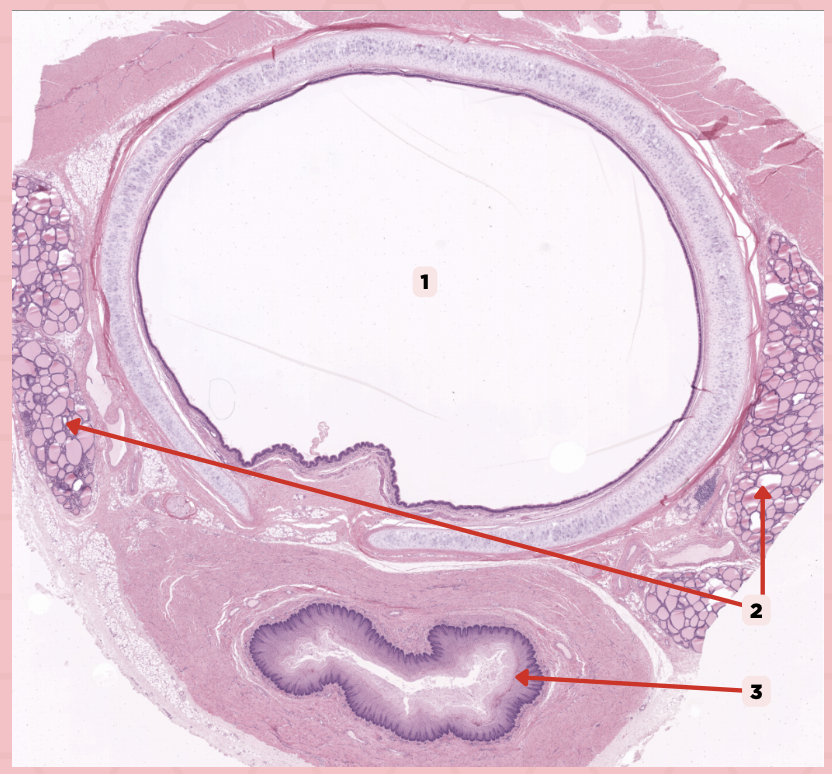

Lamina Propria

Identify the structure labeled as 1.

Adipocytes

Identify the structure labeled as 2.

Keratinized stratified squamous epithelium

Identify the structure labeled as 3.